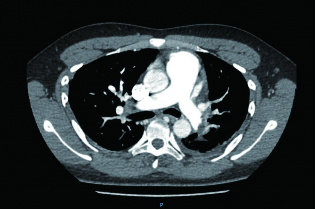

2 积极寻找补救性溶栓的治疗时机并非遥不可及例3 36岁,女性。主诉“活动后气短5 d、加重伴咯血1 d”。既往因月经不调,应用激素替代治疗20 d;否认手术、外伤及制动史。入院查体:神志清楚,体温36.8℃,血压110/75 mmHg,脉率118次/min,呼吸23次/min,脉氧饱和度90%(安静,空气氧),轻度乏氧征。双肺呼吸音清。心率118次/min,未闻及干、湿性啰音,心律齐,P2 > A2,心界无扩大,无杂音,腹软,无压痛,肠鸣音正常,双下肢无浮肿。神经系统查体未见异常。血气分析(空气氧)提示pH 7.415,PaCO2 38.3 mmHg,PaO2 89.90 mmHg,SaO2 89.90%;D-Dimer 1 684 ng/mL;FDP 8.670 μg/mL,FBG 3.510 g/L;PLT 151.0 G/L;cTnI 0.00 ng/mL,BNP 58.00 ng/mL;ALT 27 U/L,AST 17 U/L,CREA 53.7 μmol/L,血Na+、K+、Cl-大致正常;UCG提示:右室壁运动减低,左室壁运动不协调,各室壁厚度正常,三尖瓣环位移14 mm,右室面积变化率19%,各瓣膜形态及运动未见异常,收缩期三尖瓣房侧见少量反流信号,T1法估测SPAP:24 mmHg;双下肢静脉超声提示:右下肢深静脉血栓形成。心电图(图 8所示)提示窦性心动过速;CTPA提示双肺主干明确充盈缺损(图 9所示)。入院诊断:急性PE(中低危)。给予低分子肝素抗凝治疗。入院24 h内,大便时出现胸闷、心悸主诉,SpO2由93%(不吸氧)降至88%(储氧面罩吸氧,Flow 10 L/min);D-Dimer由入院时1 026 ng/mL升至4 100 ng/mL,血压110/70 mmHg。因血氧有恶化趋势遂决定给予静脉溶栓治疗(r-tPA 50 mg,2 h内泵入),溶栓治疗结束后2 h复查凝血提示D-Dimer 45 000 ng/mL。溶栓2 h患者症状明显好转;心电图提示窦性心动过速,SⅠQⅢTⅢ征象较前改善,胸前导联出现冠状T波(图 10所示)。溶栓后24 h复查CTPA右肺主干血栓明显消失,右心室较前明显缩小(图 11所示)。

| 图 9 入院时CTPA提示右肺动脉主干充盈缺损、左肺亚段水平充盈缺损、右心室增长 |